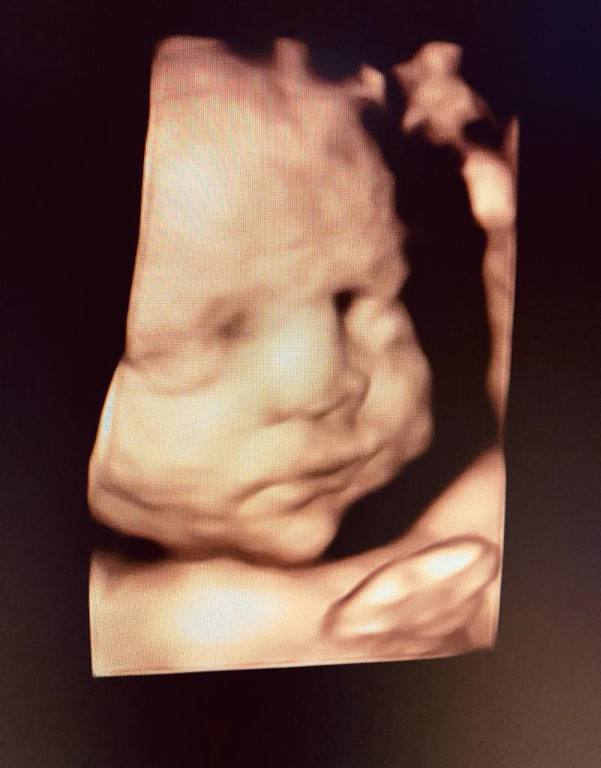

Atención de parto

Envíado por Dra. Erika Lissette Palacios